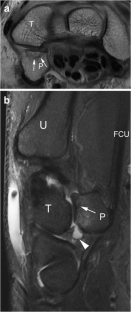

Pisotriquetral joint disorders: an under-recognized cause of ulnar side wrist pain

Pisotriquetral joint disorders are often under-recognized in routine clinical practice. They nevertheless represent a significant cause of ulnar side wrist pain. The aim of this article is to present the main disorders of this joint and discuss the different imaging modalities that can be useful for its assessment.